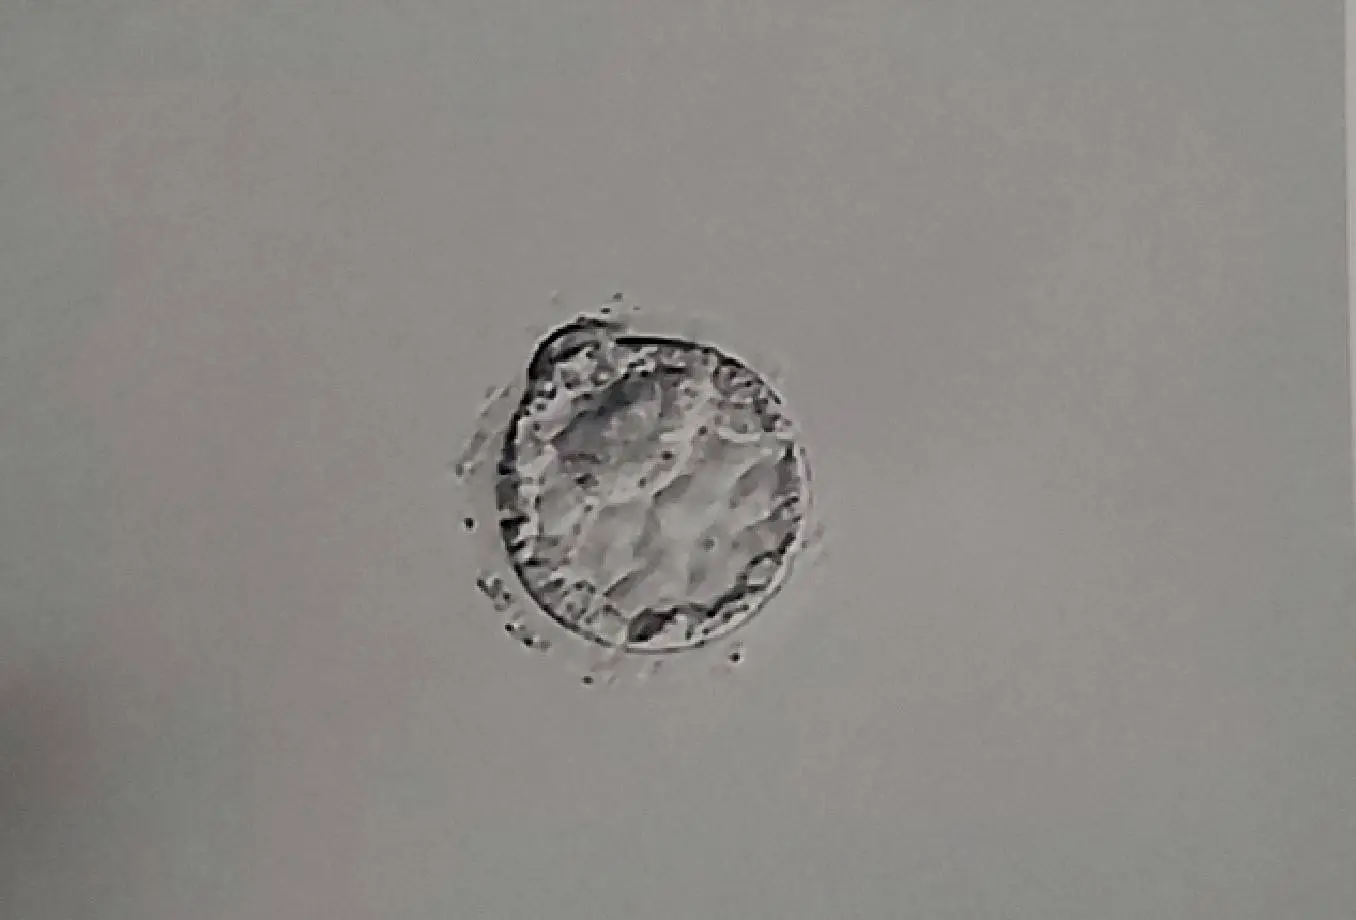

ダイレクト分割(異常分割)の胚は移植すべき?胚盤胞培養が推奨される理由

不妊治療、特に体外受精(IVF)において、受精卵(胚)の分割スピードや様式は、その後の妊娠率を左右する重要な指標です。

近年、タイムラプスインキュベーターの普及により、「ダイレクト分割(direct cleavage)」と呼ばれる特殊な分割様式が注目されるようになりました。

通常、受精卵は1細胞→2細胞→4細胞→8細胞と規則正しく分割していきます。

しかし、ダイレクト分割は、1細胞から一気に3細胞へ、あるいは2細胞から5細胞へと、段階を飛ばして分割してしまう状態を指します。